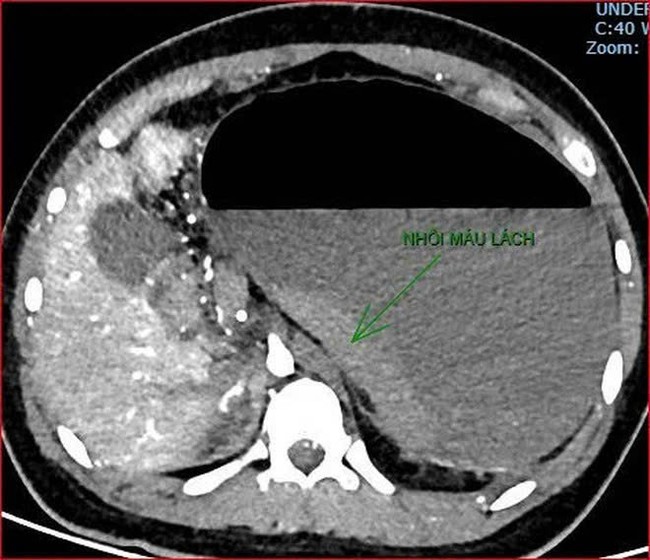

Khoảng 21h40, kết quả chụp CT cho thấy bệnh nhân rơi vào tình trạng cực kỳ nặng và hiếm gặp, bao gồm: Xoắn dạ dày, nhồi máu thận trái, nhồi máu lách, viêm đầu tụy, viêm hỗng tràng, kèm dịch ổ bụng và tràn dịch màng phổi, trên nền bệnh nhân mắc hội chứng Down và tim bẩm sinh.

kết quả chụp CT cho thấy bệnh nhân rơi vào tình trạng cực kỳ nặng và hiếm gặp.